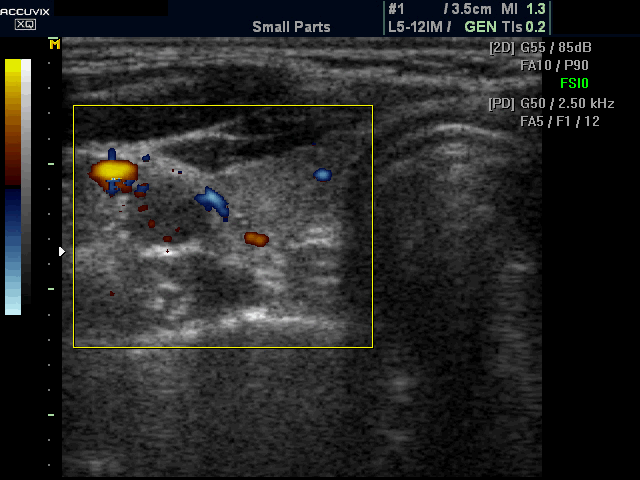

现在彩超的精准性和敏感性远优于过去,即便是2~3毫米的小结节也能清晰检出,导致原来没发现的疾病如甲状腺结节(包括甲状腺癌)被发现。

过去颈部不作为常规体检的筛查项目,现在甲状腺癌彩超普及了,筛出的病例相对就多了。